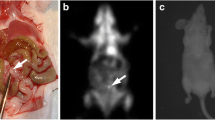

To gain more accurate anatomical localization of the peritoneal metastasis, especially depth information, we developed a 3D bioluminescence and fluorescence imaging method using IVIS Spectrum apparatus with living image version 4.2 software (Fig. 5a). When merged, both luminescence and fluorescence images were almost colocalized in all three directions. Therefore, we next fused optical images with MRI images. The resultant multimodality imaging could successfully specify the anatomical site of peritoneal metastasis in the omentum, which is located below the stomach and right side of the spleen (Fig. 5b). This anatomical diagnosis proved to be accurate in light of autopsy findings (Fig. 5c).

Multimodality imaging with combination of 3D optical imaging and MRI for peritoneal metastasis. a 3D bioluminescence and fluorescence images for metastasis constructed by Ivis spectrum. Colocalization of luminescence image (green) and fluorescence image (red) for metastasis is clearly seen (arrows). b Multimodality images constructed by fusion of optical images and MRI image. Anatomical localization of peritoneal metastasis (arrows) at the omentum (below stomach and right side of spleen) is apparent with MRI image. c Autopsy finding confirmed the diagnosis by multimodality imaging. Bars 5 mm